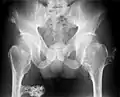

Multiple osteochondromas causing deformity of the forearm (shortening of the radius with secondary bowing of the ulna) -

Multiple osteochondromas at the pelvis -